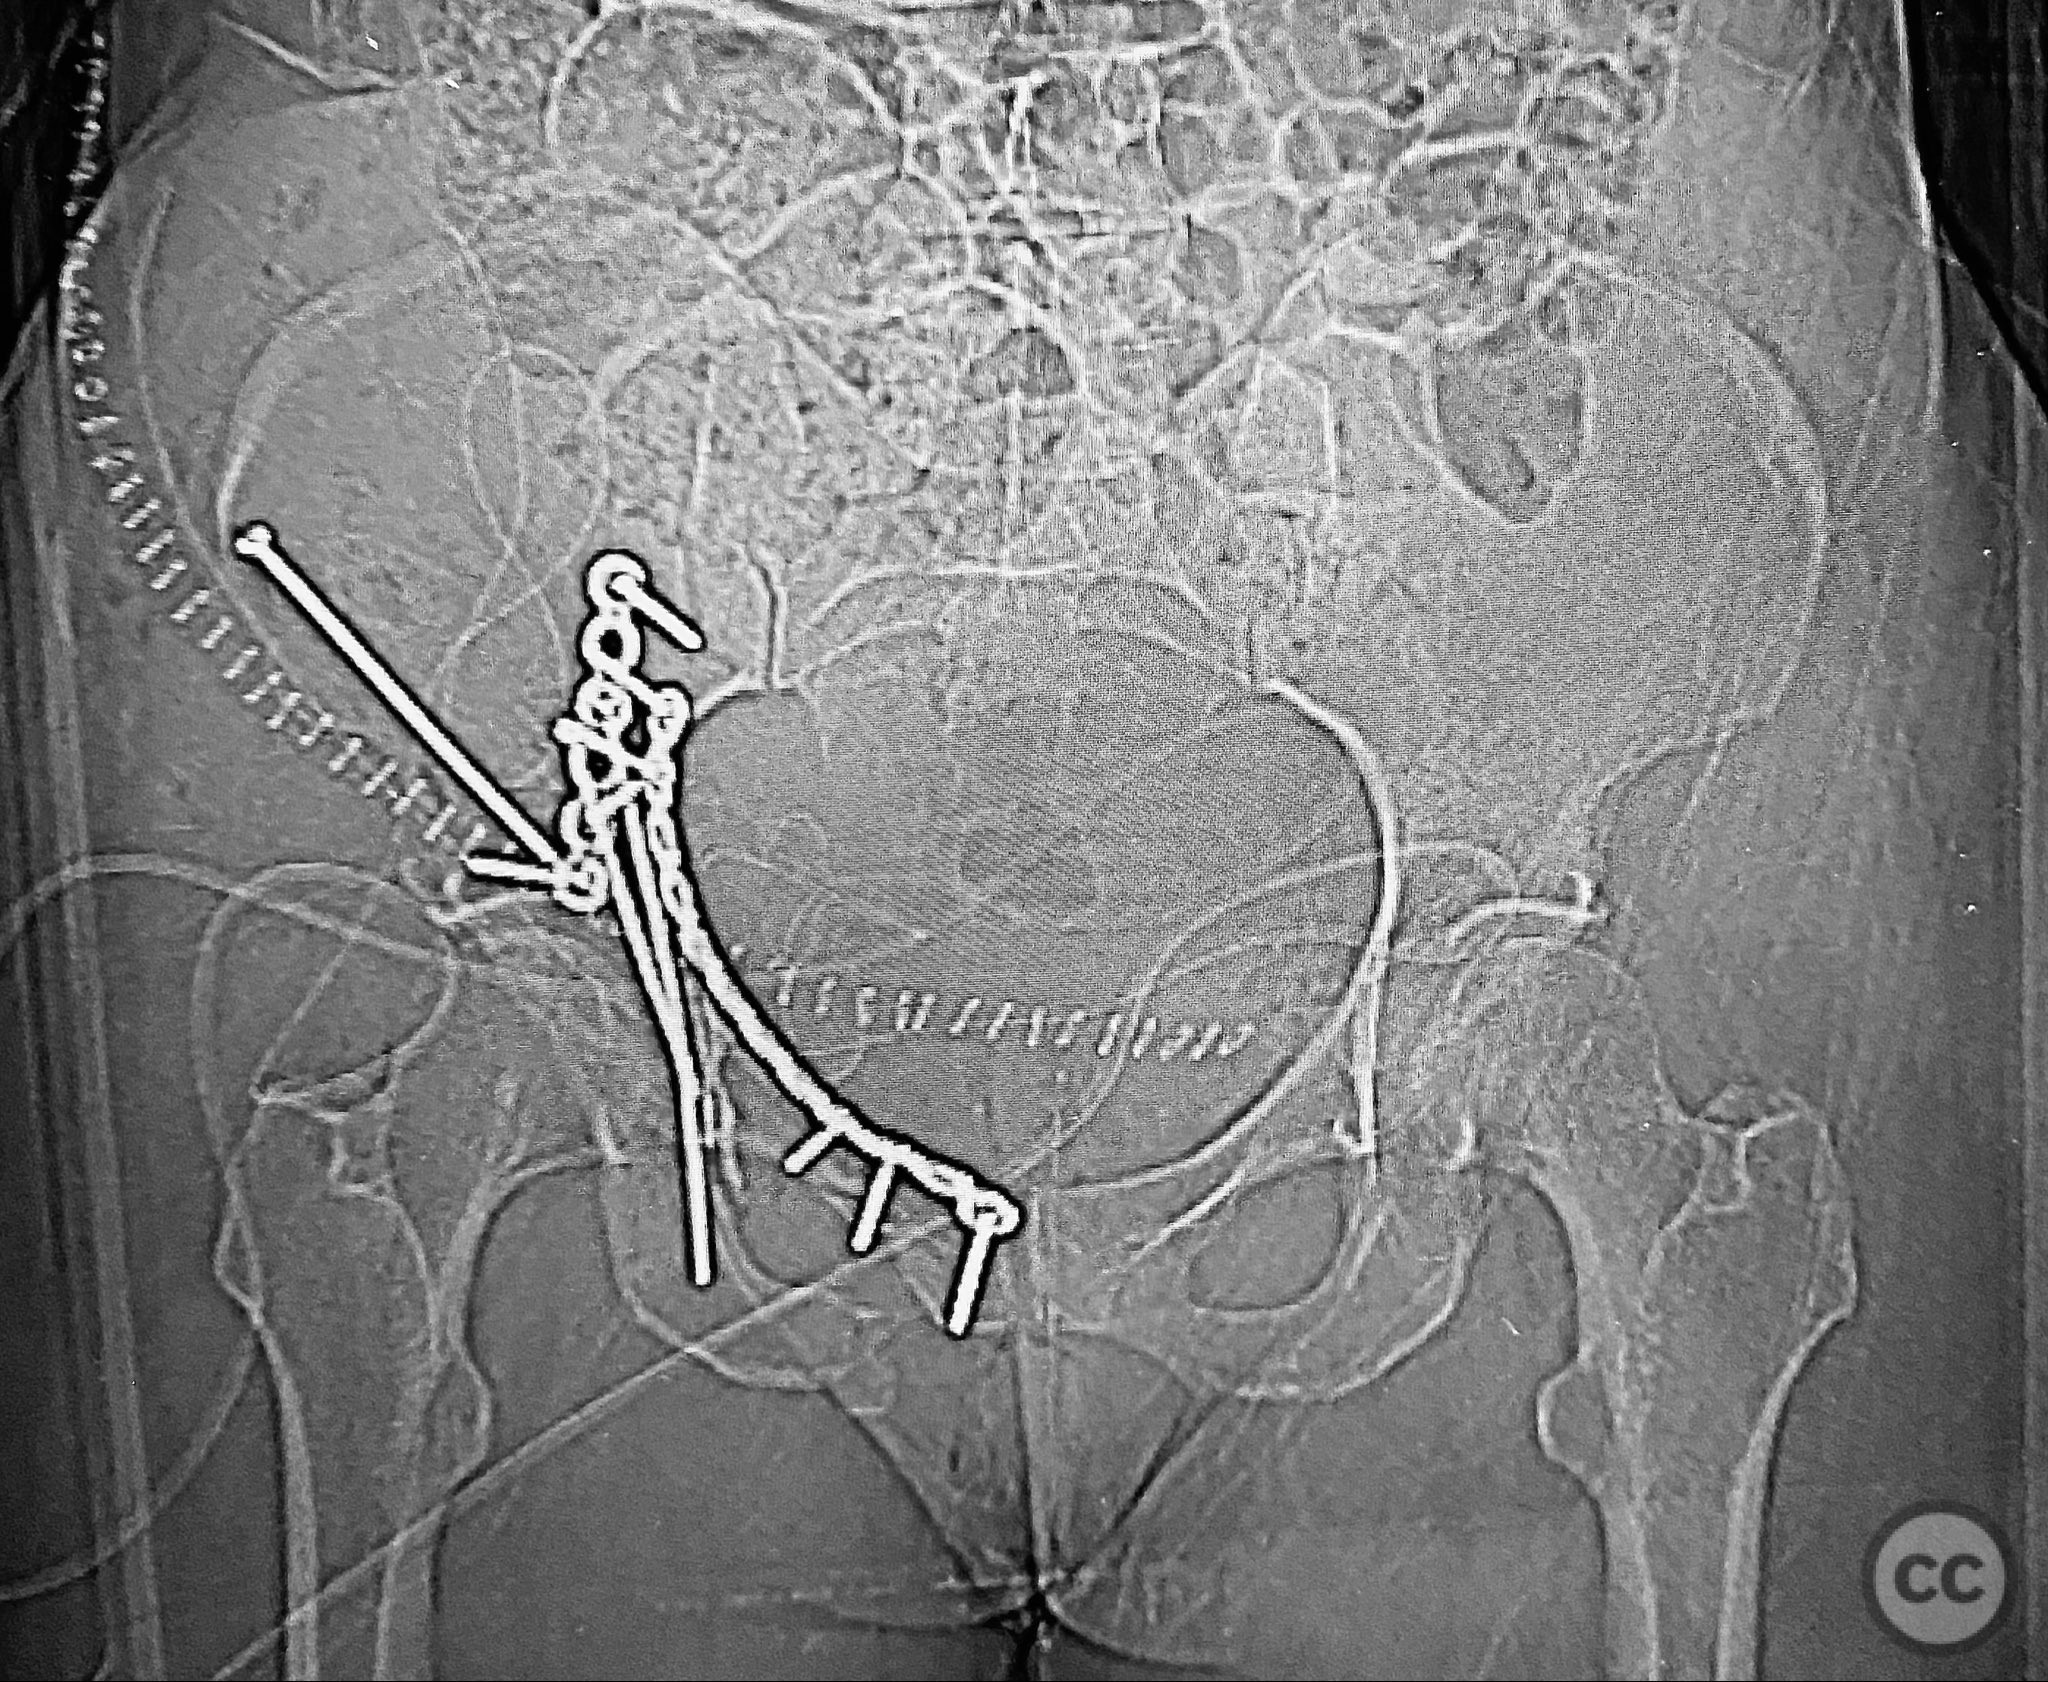

The anterior column fragment was reduced first under direct visualization and held with a 6-hole plate and lag screw. The 12-hole intrapelvic plate was then contoured and applied along the pelvic brim to reinforce the reduction. The posterior column and posterior wall fragments, including the dome component, were stabilized with lag screws placed through safe osseous corridors under fluoroscopic guidance. The independent AIIS fragment was addressed during the exposure and incorporated into the reduction construct. The parasymphyseal injury zone was inspected for stability following fixation. Postoperative CT confirmed anatomical reduction and stable fixation of all fragments.

Orthopaedic implants used:   6-hole reconstruction plate, 12-hole intrapelvic plate, multiple lag screws